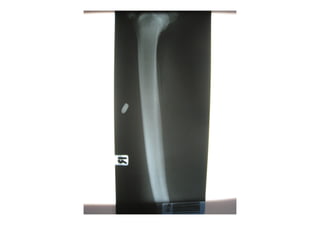

ชายไทย อายุ 38 ปี

อาชีพช่างรับเหมาก่อสร้า

ถูกยิง 3 นัดที่ท้องและขาซ

ก่อนมา รพ.ครึ่งชั่วโมง